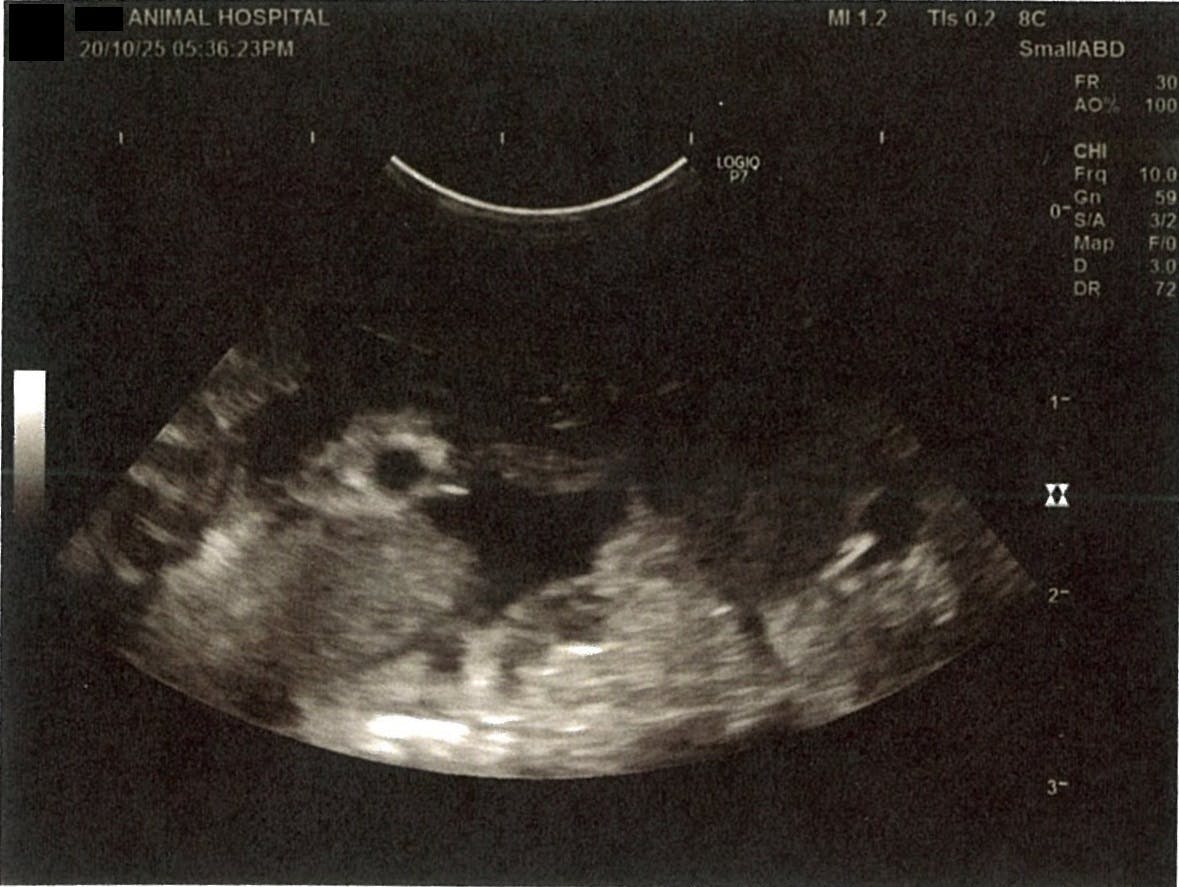

《心臓周りの胸部以外の全ての腹部で腹水がみられるとの診断です》

大網という部分で内臓を包む膜のようなものです。その周りに腹水が溜まっています。

左腎臓周りに腹水が確認できるエコー写真